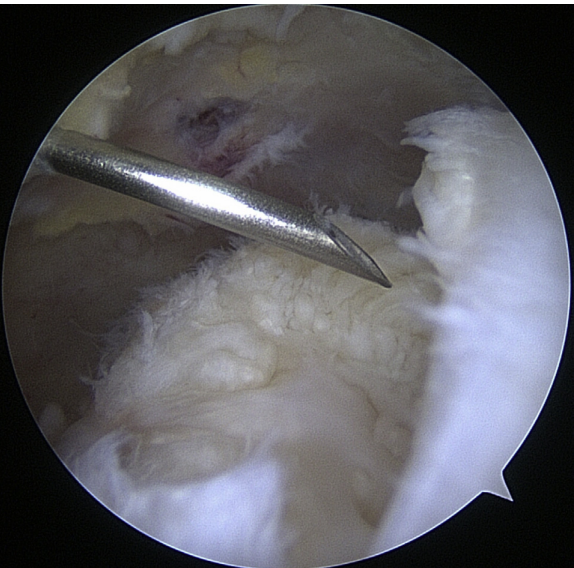

Instrumentation

When it comes to shoulder arthroscopy, the most common arthroscope utilized is the 4.0 mm 30 scope. A 30-magnification scope is sufficient for most situations. An arthroscopic-assisted coracoclavicular reconstruction, subscapularis repairs, Remplissage procedures, glenohumeral ligament lesions, and humeral avulsion can all benefit from the use of a 4.0-mm 70 arthroscope, which should always be on hand. There should be a large selection of cannulas accessible, and they will differ according on the operation being carried out.25

As the principal penetrating instruments, 5.5-mm blunt-tipped cannulas are often used for portal insertion. Blunt tips are preferred to reduce the likelihood of iatrogenic harm, especially to articular cartilage. Because they are easily passable by the majority of arthroscopy passing devices, 8.25-mm cannulas are often employed for “instrumentation” portals. In addition, cannulas of 6.5 mm or less are commonly used in suture management. Cannulas that are threaded or have locking mechanisms are preferable since they are less likely to come free from the joint. In most cases, one of two methods can be employed: gravity or a pump system. Sufficient management of pressures, usually approximately 60 mm Hg, is necessary to avoid significant soft-tissue edema, which can complicate the use of cannulas and instruments.25

Standard Portal Placement

A traditional posterior portal would be placed at the “soft spot” of the infraspinatus’s raphe. The standard placement is 2 centimeters inferior and 2 centimeters medial to the posterolateral border of the acromion, however this can change according to the patient’s size. It is possible to make a portal incision after inserting an 18-gauge spinal needle into this region to roughly follow the correct course. The posterior capsule is shattered by inserting a blunt trocar into the joint and directing it toward the coracoid.6

Preliminary surgical planning will establish the exact location of the anterior portal. Arthroscopy techniques for rotator cuff or biceps tenodesis usually include positioning the anterior portal centrally in the rotator interval, near the subscapularis tendon. It is common practice to use two anterior portals while performing arthroscopy on labral disease. The anteroinferior portal, which is often the working portal, is typically located around the subscapularis tendon. An extra portal called the anterosuperior portal may be used for suture inspection or shuttletling without damaging the supraspinatus tendon. Its location is directly above the biceps tendon or just slightly ahead of it. A common technique for creating these portals is the “outside-in” approach, which involves inserting a spinal needle under direct arthroscopy view to determine the correct portal location.6

Setup

The coracoid, acromioclavicular joint, clavicle, and acromion are all marked on the skin. If subacromial work is going to be performed, the subacromial bursa may be infiltrated with up to 30 cm3 of a mixture of 0.25% bupivacaine and epinephrine. A standard posterior portal is the typical site of access to the subacromial area and glenohumeral joint. The typical placement of this opening is 2 centimeters medial and 2 centimeters distal to the posterolateral border of the acromion. Palpating the soft tissues of the posterior glenohumeral joint is a common way to confirm the proper position. An anterior portal develops after the joint has been inserted. Figure 4 shows that the surgeon has the option of employing a spinal needle to perform it from the outside in or an inside out approach, depending on his or her choice. The anterosuperior portal is located just off the outside edge of the acromion. You may find the anteroinferior portal directly on the side of the coracoid. One centimeter below the anteroinferior portal is the 5 o’clock portal, which is defined as passing through the subscapularis tendon. Scientists say this entry point is the most common and least invasive as it mimics neurovascular systems. Any anterior portal may be used to conduct basic shoulder arthroscopy. Figure 5 shows the setup of both anterior portals for biceps tenodesis, subscapularis repairs, and labral repairs. For posterior labral repairs, spinal needle localization allows for the creation of an auxiliary posterolateral portal situated immediately distal to the posterolateral limit of the acromion. Anterior positioning of the Wilmington portal, one centimeter laterally to the posterolateral margin of the acromion, is recommended for superior labral repairs. The posterolateral and Wilmington portals are types of trans-rotator cuff tendon access points. Cannulas with the smallest diameters necessary should be used.25

The subacromial region may be accessed via the posterior portal if needed after any intra-articular procedures are finished. Spinal needle localization allows for the creation of a lateral portal, typically 2 cm laterally to the acromion’s lateral border and aligned with the clavicle’s posterior border (Figure 6). For any subacromial surgery, pre-positioned anterior portals may be used (Figure 7). An extra Neviaser portal may be made underneath the spinal needle localization, precisely below the acromioclavicular joint, if that becomes essential. This may be useful for a variety of suture procedures, including those involving the superior labrum, the rotator cuff, and the decompression of the suprascapular nerve (Figure 8).25